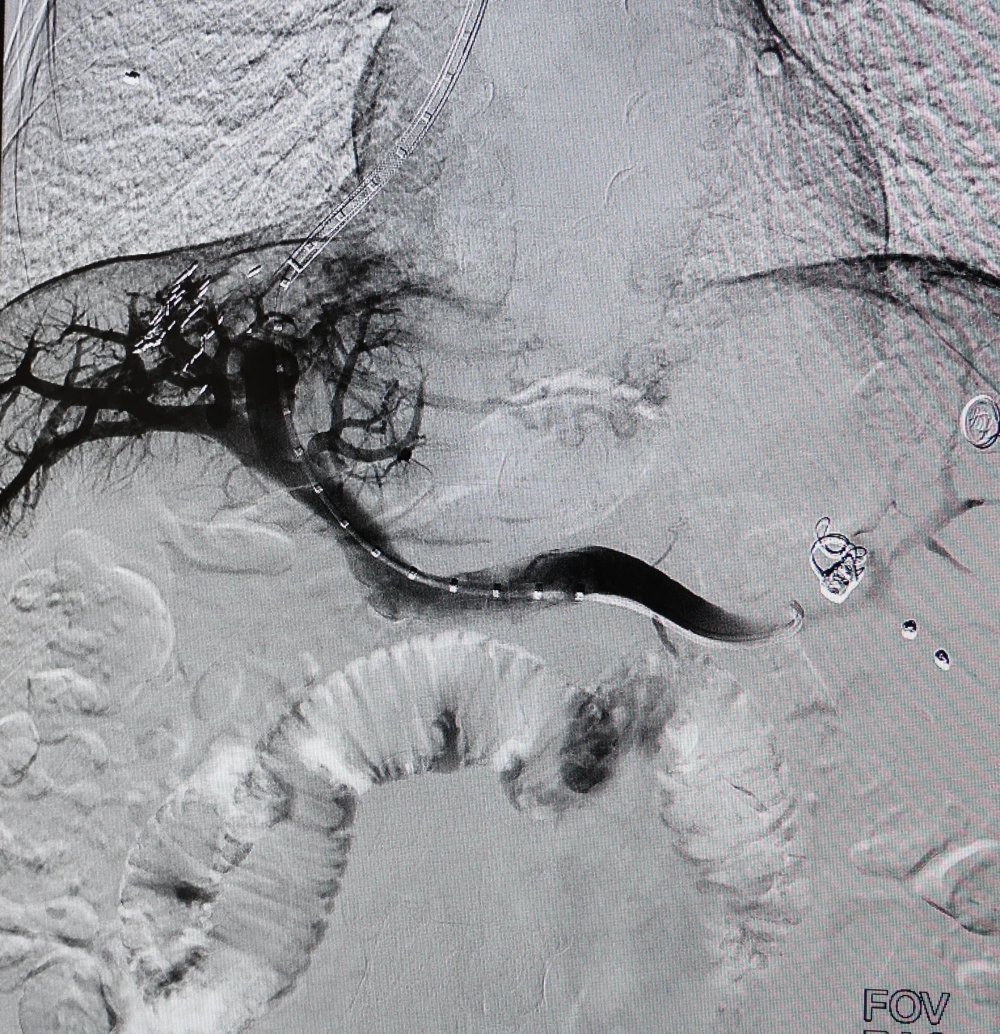

5月15日,手术按计划进行,在卜高峰及其团队的配合下,张明主任首先经颈静脉穿刺,引入导管至肝静脉,随后在DSA影像引导下精准穿刺肝内门静脉分支,建立肝静脉-门静脉通路。导丝通过后,球囊扩张分流道,并成功植入覆膜支架,用一根导丝,在患者肝脏内架起了一座生命“立交桥”,整个手术历时不到1小时。术中患者处于清醒状态,无明显不适,术后患者门静脉压力显著下降,生命体征平稳。